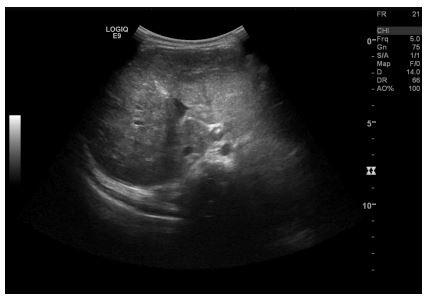

Abdominal sonography (Fig. 1) confirmed hepatomegaly (10,6cm) and numerous nodular formations suggestive of metastatic lesions, the largest measuring 21mm. No other ultrasound abnormalities were detected, namely space-occupying lesions in the adrenal gland areas or along the paravertebral space. Chest radiography was normal.

In this case, a more frequent follow-up schedule was chosen: an appointment every four weeks until a reduction in liver lesions size was observed, involving a clinical, laboratory and ultrasound evaluation. Clinically, there was a progressive decrease in abdominal circumference, with no other symptoms reported. Laboratory follow-up revealed a favourable course, with normalization of aminotransferase, catecholamine excretion and liver size after eleven months (table 1). Radiologic follow-up was performed by abdominal ultrasound, revealing a normalisation of adrenal gland and liver dimensions three and nine months post-diagnosis, along with progressive involution of the hepatic lesions (Fig. 4). By the 11-month follow-up, a normal abdominal ultrasound was reported.